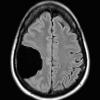

10A1 Ulegyria (Case 10) FLAIR 2

10A2 Ulegyria (Case 10) FLAIR 3

10A3 Ulegyria (Case 10) FLAIR 4

10A4 Ulegyria (Case 10) FLAIR 5

10A5 Ulegyria (Case 10) T2W 2

10A6 Ulegyria (Case 10) T2